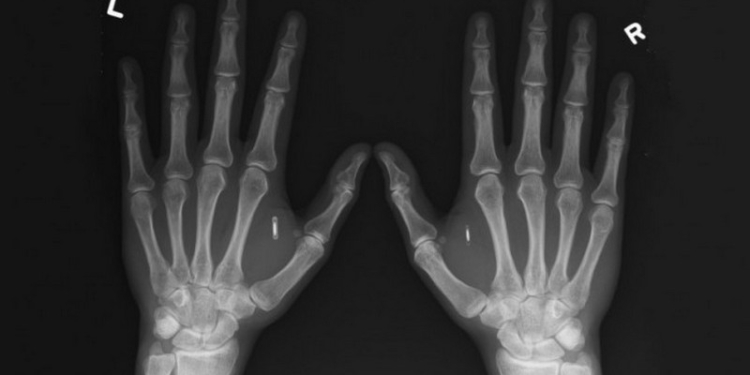

В Одессе на конференции Black Sea Summit немецкий профессор вживил в руку киевлянина Евгения компьютерный чип, сообщил «Культурометр». По заверениям издания, Евгений стал первым человеком, которому провели подобную процедуру в Украине.

Евгений получил бесплатно чип Dangerous Things xNT-Implant, который оценен в 89 евро. Емкость накопителя составляет 880 байт.